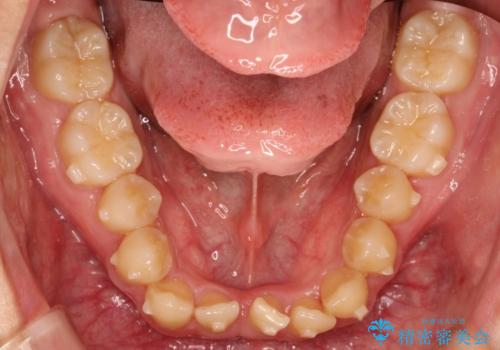

- 前歯のがたつきが気になるとのことで来院されました。

骨格的なところと、上下の歯の大きさのことを考慮して、下の前歯を1本抜歯し、インビザラインにて矯正治療することとなりました。

上の前から2番目の歯がもともと小さかったため、最後にかぶせ物を装着することで、自然な仕上がりにできました。